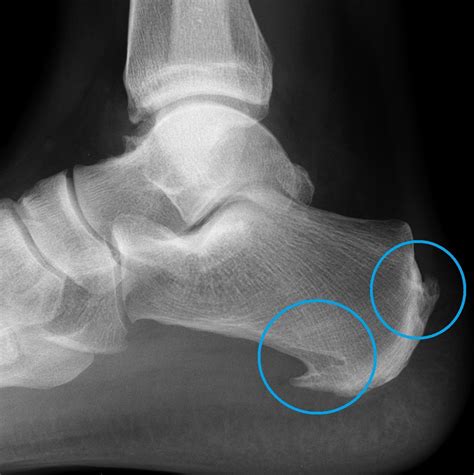

A bone spur, medically known as an osteophyte, is a bony growth that develops along the edges of a bone. When it occurs in the heel, it is typically located either on the underside of the heel bone (calcaneus) or at the back of the heel near the Achilles tendon. These growths occur as the body’s response to long-term stress, pressure, or inflammation.

The development of bone spurs in heel is often a slow, gradual process. As your body attempts to repair injured or stressed areas, it deposits extra bone material. Over time, this results in a visible or palpable bump. It is important to note that the spur itself is not always the direct source of pain; rather, it is often the surrounding tissue inflammation that causes discomfort.

Recognizing the signs of this condition is crucial for timely management. Many people live with bone spurs without even knowing it until an X-ray reveals them. However, when symptoms do arise, they can be quite debilitating.